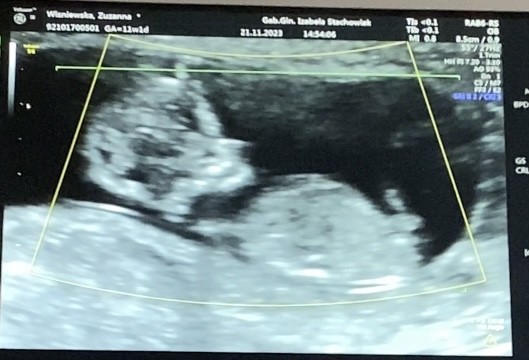

Dla mnie nadal na tym zdjęciu nie można na 100% potwierdzić, że to penis. Dla mnie raczej wygląda na nogę, albo właśnie pępowinę. U mnie wyglądało to tak jakoś w 11tc:

Natomiast my tu wróżymy ze zdjęcia - a lekarz jednak robiąc USG może sobie obejrzeć dziecko z różnych perspektyw itd. więc raczej ufałabym lekarzowi - szczególnie jeżeli ma dobry sprzęt i certyfikat.